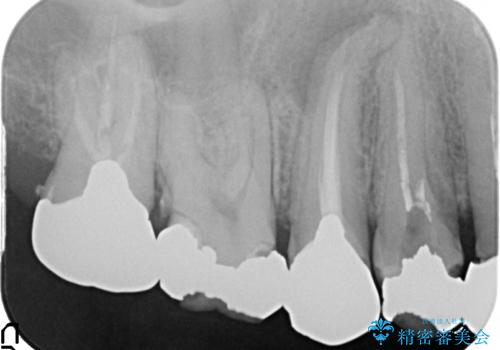

- 歯がない左側でものが咬めず、右側で咬むと歯が痛むので診て欲しいといらっしゃった方の症例です。

根尖病変が認められる歯は再根管治療を行い、歯根が破折していた左上4は抜歯しました。

インプラントは希望されなかったため、左側は1番から7番のロングスパンブリッジによる補綴を行いました。